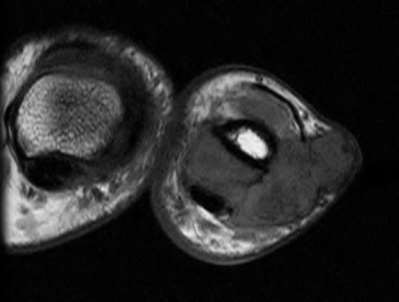

A 35-year-old woman reports wrist pain after a fall onto an outstretched hand. On exam, she has focal tenderness over the wrist snuffbox. A radiograph and CT image are shown in Figures A and B. What is the proper treatment of her injury?